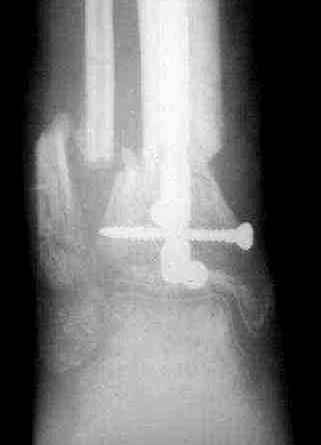

5, 6 - через 2,5 мес после травмы выполнен закрытый остеосинтез блокируемым штифтом.

7, 8, 9, 10, 11 - через 8 мес после травмы перелом сросся.

Пациент ходит без дополнительной опоры, не хромает (видеоролик выложил сюда